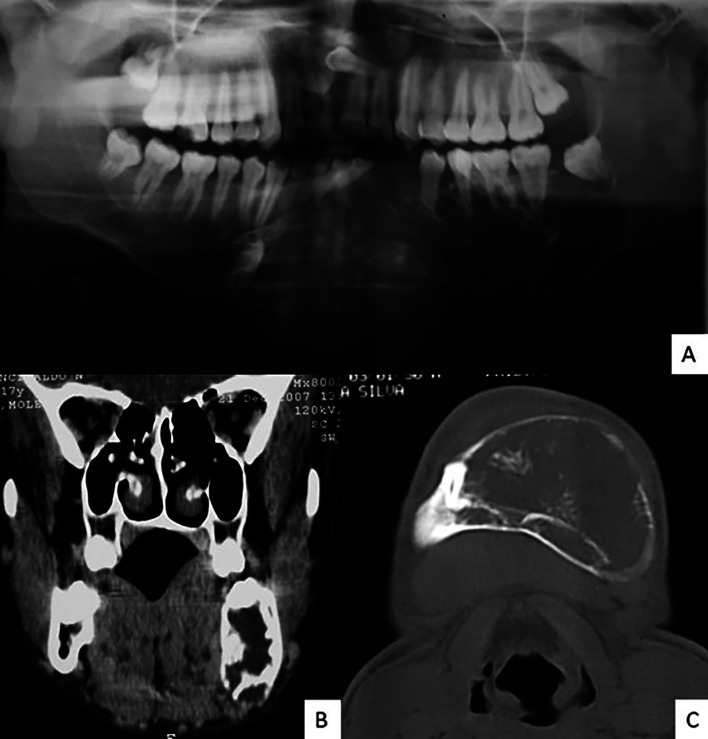

Odontogenic myxoma is an odontogenic tumor of mesenchymal origin that presents locally invasive behavior. Its treatment is surgical, and the approach can be more conservative or radical. This article presents the rehabilitation of a patient with extensive odontogenic myxoma in the mandible treated conservatively with follow-up for 14 years. A 17-year-old male patient sought care with a painless swelling in the mandibular region causing facial asymmetry. Imaging exams showed a mixed image, with intralesional septa, involving the left anterior and posterior regions of the mandible with a small remaining basilar and lingual bone. An incisional biopsy was performed which confirmed the diagnosis of odontogenic myxoma. Due to the extent of the lesion, a conservative approach was chosen, with excision of the lesion and peripheral ostectomy, with recurrence of the lesion after 48 months, with a new approach being performed. After 14 years of follow-up, without further recurrence of the lesion, the patient was rehabilitated with dental implants and protocol-type prosthesis. Conservative treatment led to bone remodeling and enabled patient rehabilitation with oral implants and an implant-supported prosthesis. Thus, conservative treatment of odontogenic myxomas is a viable alternative for similar cases, and its longitudinal postoperative follow-up is essential. Key words:Conservative Treatment, Dental Implants, Myxoma; Oral Pathology, Oral Surgery.